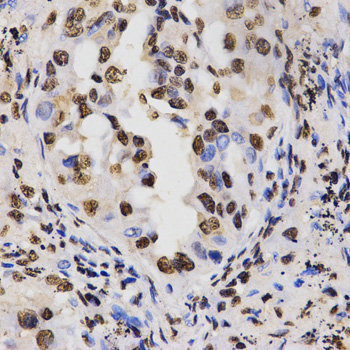

Immunohistochemistry of paraffin-embedded human lung cancer tissue using H3R17me2a antibody at dilution of 1:200 (x400 lens)